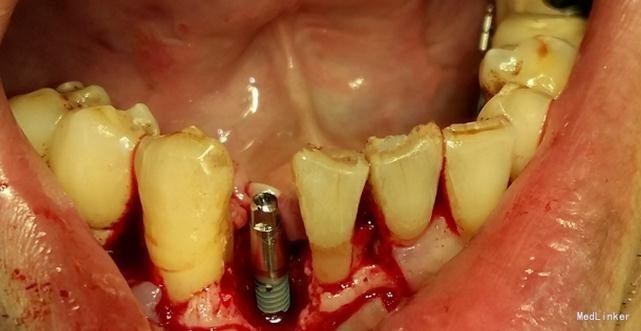

患者,男,45岁,右侧下颌侧切牙严重龋坏,拔除后要求种植修复,平素体质一般,无药物、食物过敏史,无高血压、心脏病等系统病史

牙科CT检查骨量适中,适合种植

种植修复